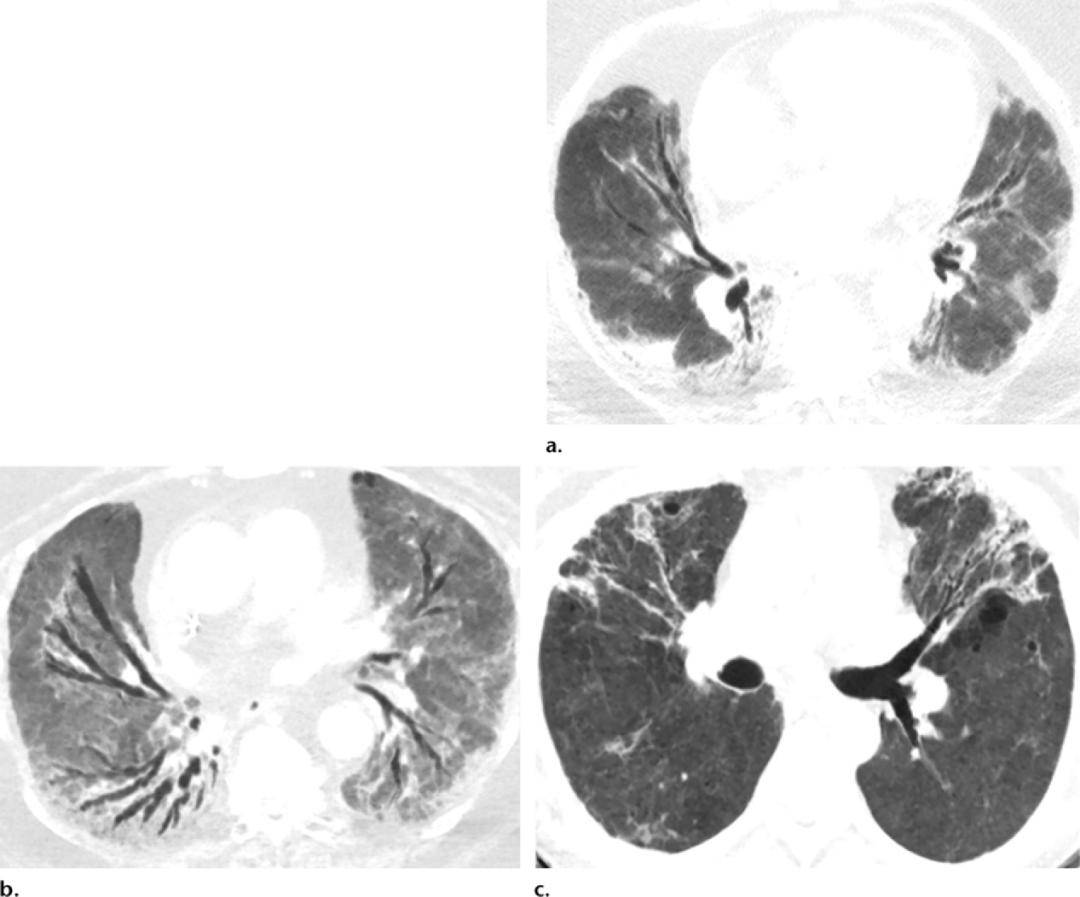

(a)就诊数天后横断面ct显示轻度柱状支气管扩张.